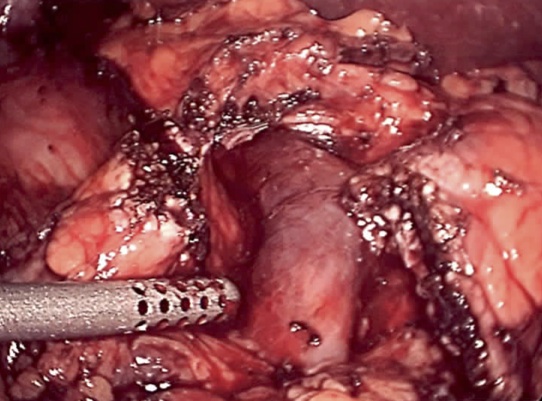

With many years experience as a liver transplant surgeon, Dr. de la Torre was the first to perform a major liver resection laparoscopically in the state of New Jersey, and has been performing laparoscopic liver surgery since 2007. Dr. de la Torre has 25 years of experience in surgery of the liver, pancreas, bile ducts, management of cirrhosis, portal hypertension, and liver cancer. Dr. De la Torre specializes in tissue sparing laparoscopic liver surgery in patients with cirrhosis, allowing the possibility of avoiding liver transplant for tumors located in the liver that were once deemed not feasible to remove. Dr. de la Torre published "A Sling Technique For Laparoscopic Resection of Segment Seven of the Liver" in the Journal of the Society of Laparoendoscopic Surgery 2018 Apr-Jun; 22(2) and most recently "Sling Technique for Laparoscopic Liver Mobilization" Journal of the Society of Laparoscopic and Robotic Surgeons 2024 Apr-Jun;28(2). While most other surgeons in New Jersey start laparoscopically and eventually open, 95% of our patients start laparoscopically and end laparoscopically without compromise in surgical quality or safety.

In addition to laparoscopic liver surgery, Dr de la Torre specializes in laparoscopic pancreas surgery, performing the Whipple Procedure through a 3-4 inch incision. The pancreas leak rate has been 0%. Patients have less pain, shorter hospital stay (4-7 days) and even a lower hospital bill.